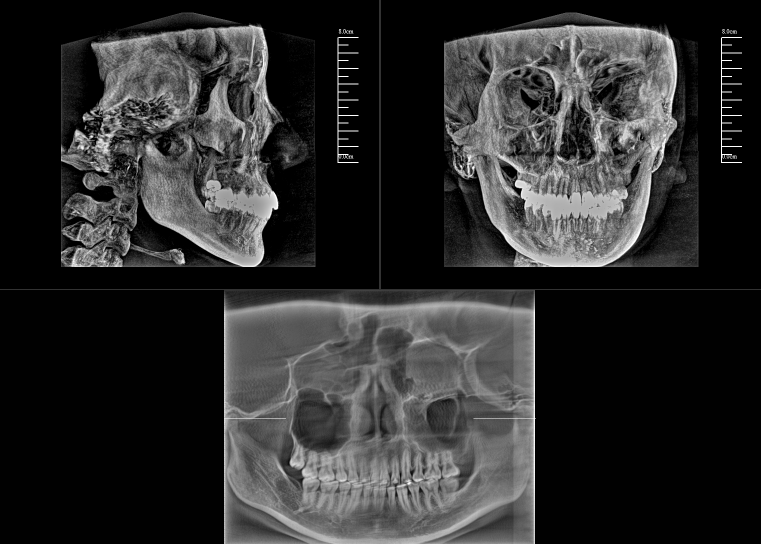

對于口腔內科疾病,牙片和全景片已具有較高診斷效果;但對于牙體牙髓病,2D成像較容易發生影像重疊的情況,無法進一步明確根管和其他周圍組織的三維信息,容易出現漏診或誤診根裂的情況。這就需要三維斷層成像,即數字化口腔CBCT。

數字化口腔CBCT是從三維的角度,即矢狀位、冠狀位和橫斷位來顯示病變組織和正常組織結構,有效的避免了2D圖像固有的缺陷,如正常組織器官的影像重疊,投射角度變化所致的影像扭曲、變形等,大大提高了診斷能力。

數字化口腔CBCT能在十幾秒時間內完成患者口腔掃描,進而生成高精度的三維影像,徹底解決了牙片機、全景機等傳統口腔X射線設備影像重疊、畸變的問題??梢?60°全方位立體觀測牙床的骨質密度、牙槽骨本身的高度、寬度等數據,不僅能重建整個顱面區的結構,對頜面骨質結構進行測量,而且還能重建精細的解剖細節。